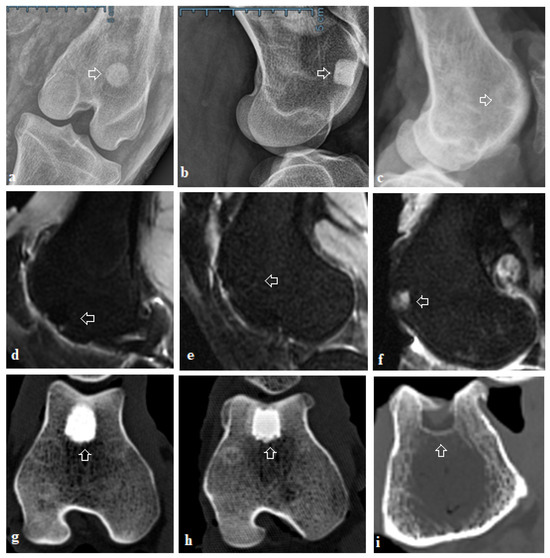

Radiological examination confirmed that the process of biodegradation of biocements was incomplete, and biomaterials were only partially resorbed. Unresorbed biomaterials appeared radiodense on both X-ray and CT images (Figure 5). Remnants of both biocement systems were present in the trabecular bone. The subchondral bone was intact. The area around the defect was homogeneous, without pathological irritation, and without osteolytic changes. The new bone was attached directly to the surface of the material, with no free spaces, gaps, or fibrous capsules between them. No swelling of the adjacent soft parts was present. We observed areas of less echogenic matter which verifies primarily the newly formed bone tissue. CT findings indicate good healing of the defects without any signs of irritation (Figure 5).

Figure 5.

X-ray, CT, and MR imaging. (a) X-ray examination of the osteochondral defect after treatment with biocement CX; in trabecular bone, the unresorbed biocement was firmly attached to adjacent bone tissue, no gap and no pathomorphological changes were observed; (b) X-ray after treatment with biocement C; no signs of tissue irritation were observed; (c) untreated defect; new bone formation is absent; (d) MRI, treatment with biocement CX; the treated defects were completely filled with the newly formed cartilage to the expected level equal to the adjacent cartilage, and tissue surface was smooth, well-defined. (e) MRI, treatment with biocement C; newly formed cartilage had a comparable thickness to the adjacent tissue, slightly hyperintense areas were visible; (f) MRI of the untreated defect; the defect in its full extent shows hyperintense and hypointense signal alterations; (g) CT image, treatment with CX, partial degradation of biocement, unresorbed part of biocement was visible under the subchondral bone, the surface of biocement was covered with new bone tissue; (h) CT image, treatment with C, biocement was not completely degraded and resorbed, and integration of the biocement with the adjacent bone was confirmed; (i) untreated defect, the osteochondral defect was not completely covered by the newly formed bone, and a large cavity remains inside the bone; arrows: indicated areas of the healed defect.

X-ray images did not indicate the presence of pathological changes, like narrowing of the joint space, the formation of subchondral cysts, osteonecrosis, or osteophytosis in the investigated groups. Similarly, there were no signs of osteoarthritis. In most cases, the new bone tissue in the untreated defects was only partially visible and was formed closer to the bone surface up to a maximum thickness of 2.5 mm, but the bone defects were not completely filled by newly formed bone. In a few cases, several defects were without any new trabecular bone formation.

2.4. Magnetic Resonance Imaging

MRI results are consistent with previous evaluations. In the CX group, the treated osteochondral defects were filled with tissue that had a well-defined surface with fine surface irregularities. The filling of the defects was at the expected level consistent with the surrounding healthy articular cartilage. The thickness of the newly formed tissue was comparable to the adjacent cartilage. The structure of the regenerated cartilage was mainly homogeneous with an isointense signal and showed no cracks and fissures. Areas with a hypointense or hyperintense signal were rarely observed. The interface between the site of the original defect and the healthy cartilage was not visible. According to the Mocart 2.0 Knee score, significant differences in the total score were seen between osteochondral defects treated with biocement CX and untreated defects (CX and untreated defect p < 0.05).

Osteochondral defects treated with biocement C showed similar results with greater surface irregularity and the presence of hypointense sections in the newly formed tissue. Adjacent areas were without signs of perifocal reactive bone oedema, only in two cases we found a border of residual bone oedema in the group treated with biomaterial C. In the Mocart 2.0 Knee score, higher values were obtained for defects treated with CX, but the differences between C and CX were not significant (Scheme 3).

Untreated defects were in most cases incompletely filled with inhomogeneous tissue. Insufficient filling of the defect or hypertrophy was visible, resulting in an uneven joint contour. Areas with hypointense or hyperintense signals were also visible. The differences between the untreated defects compared to the control sample were statistically significant (p < 0.001).

We noted different signal alterations in trabecular bone in defects treated with biomaterials, indicating incomplete biocement resorption and an ongoing process of bone remodelling with typical signs of healing. The used biomaterials CX and C did not evoke specific degenerative changes in the joint cavity nor in the surrounding native cartilage or bone. Synovitis was not noted in any of the scanned sheep.